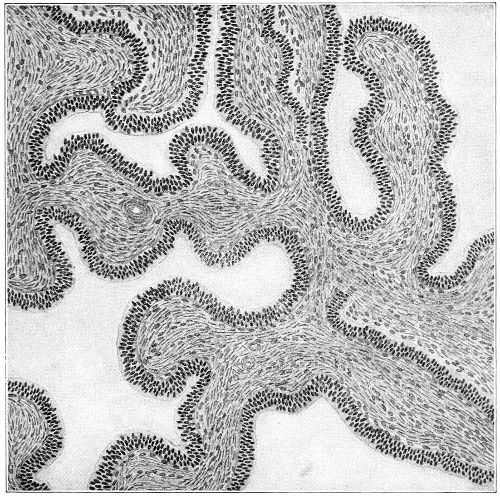

Several varieties of acute vaginitis may be recognized—the simple, the granular, the senile, and the emphysematous. It is unusual to find the entire surface of the vagina involved. The disease is confined to areas or patches separated by healthy tissue.

In granular vaginitis, which is the variety usually seen, the papillæ are infiltrated with small cells, and are much enlarged, so that the inflamed surface has a granular appearance.

Acute vaginitis is accompanied by dull pain and a sense of fulness in the pelvis. The discomfort is increased by standing, walking, defecation, and urination. There is a free discharge of serum or pus, which may be tinged with blood. The character of the discharge depends upon the variety and the period of the disease. Inspection, which can best be made through the Sims speculum, with the woman in the Sims or knee-chest position, shows the characteristic lesions of inflammation of the mucous membrane.

Acute vaginitis, if neglected, may pass into the chronic form. It usually lingers in the upper part of the vagina, in the fornices, especially in vaginitis of gonorrheal origin. By careful inspection we find here one or more granular patches of inflammation, which cause a vaginal discharge from which man may be infected, and from which infection of the upper portion of the genital tract, the uterus, and the Fallopian tubes may be derived.